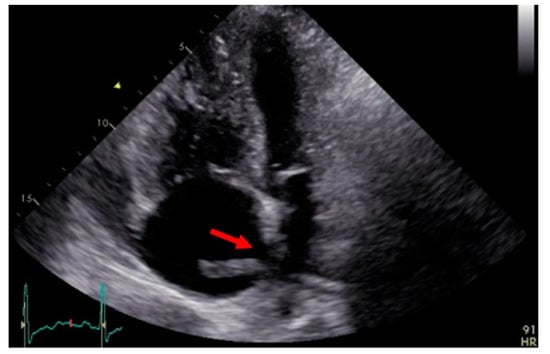

3.5. Transthoracic Echocardiography